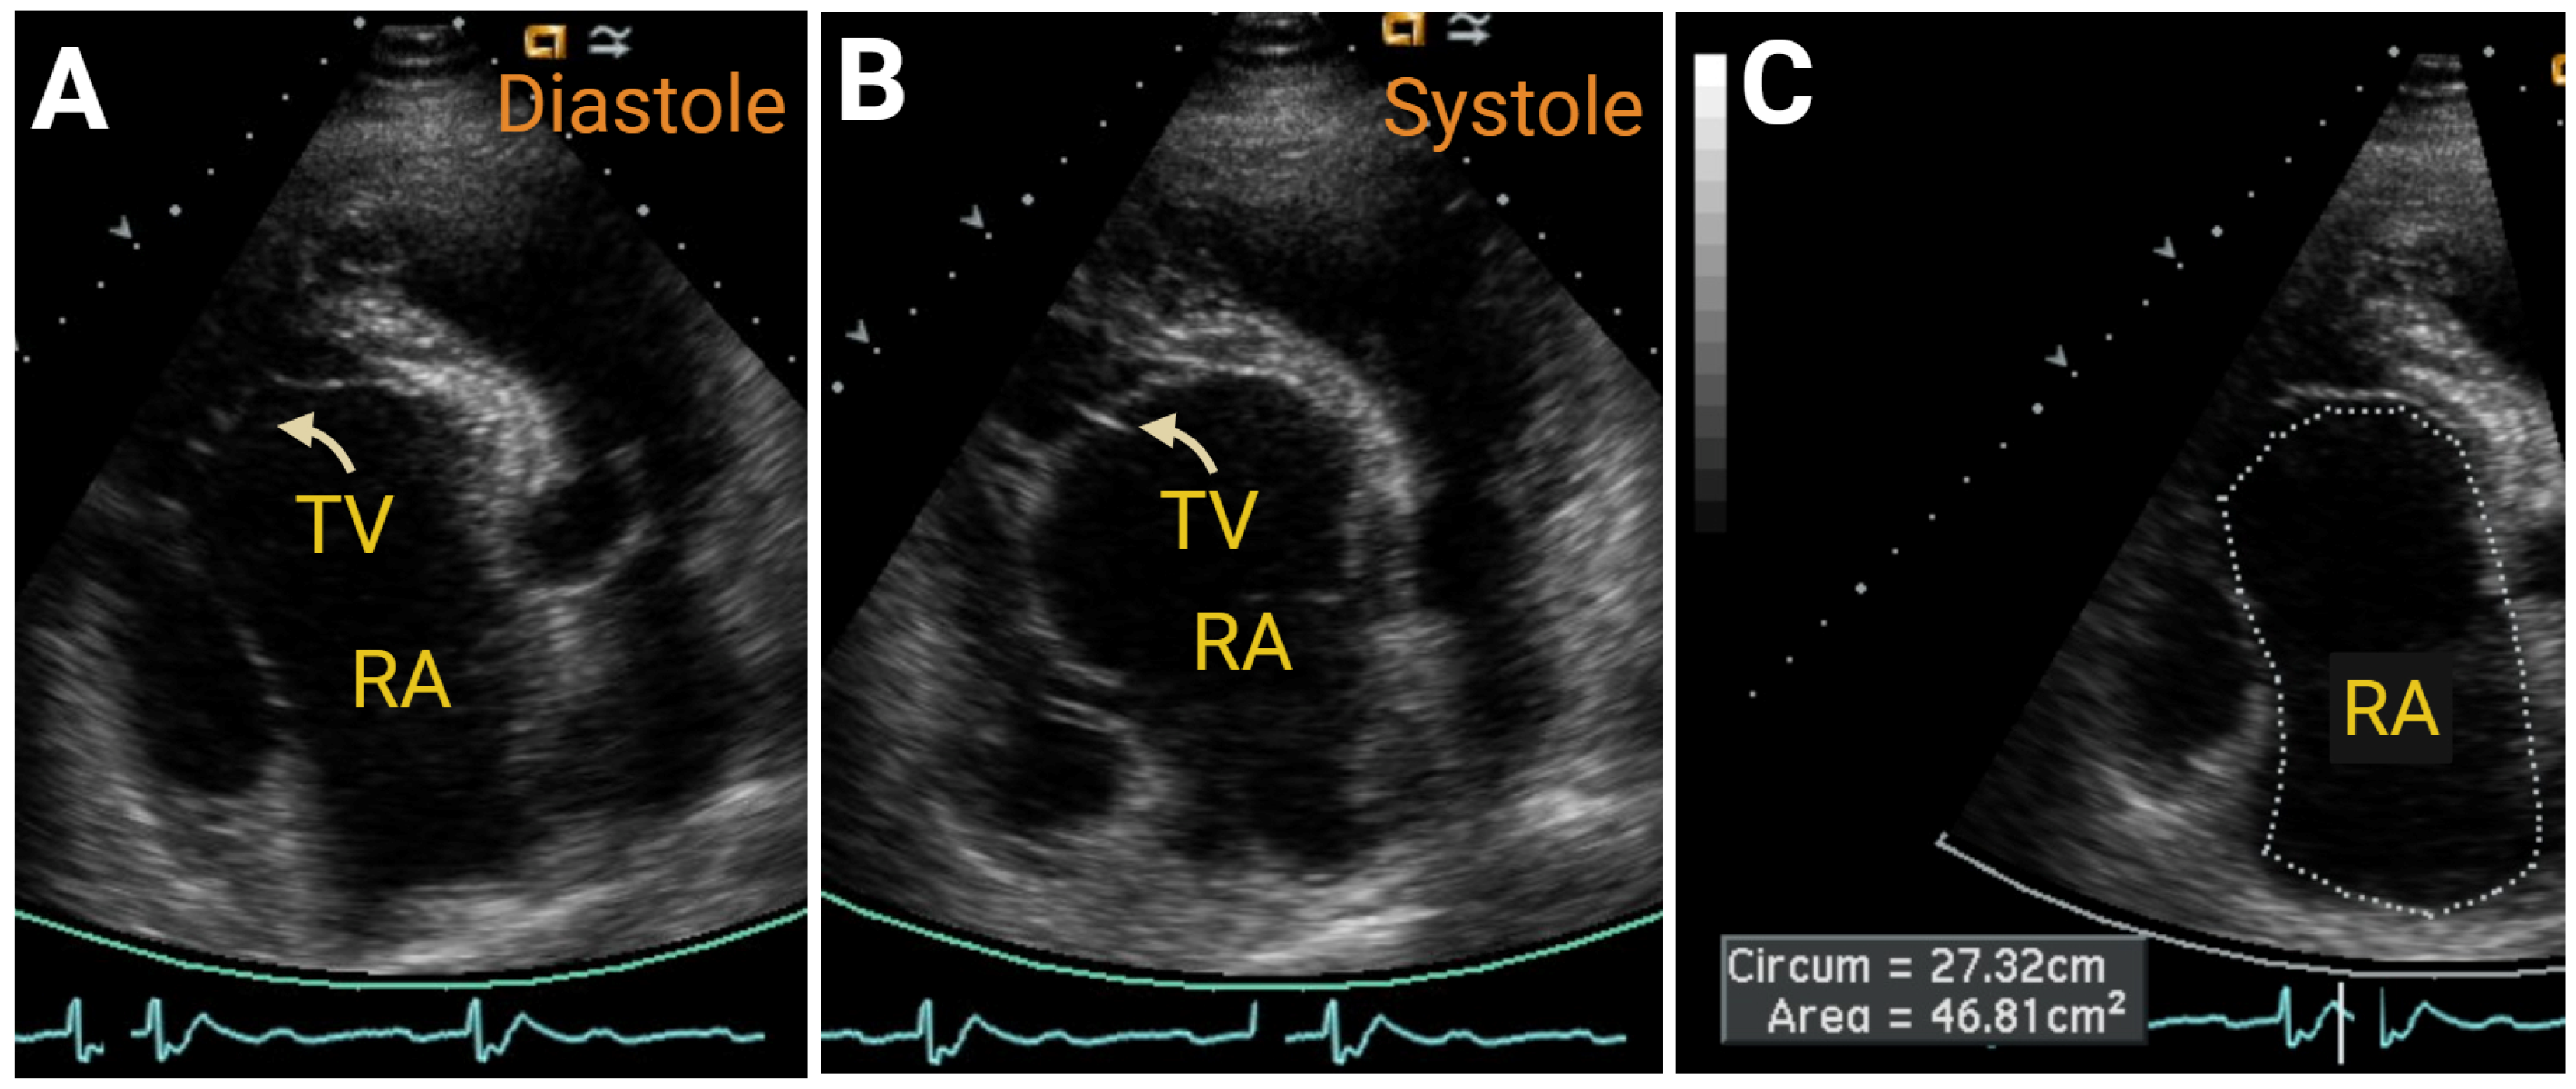

7.2.3. Simple Congenital Heart Defects